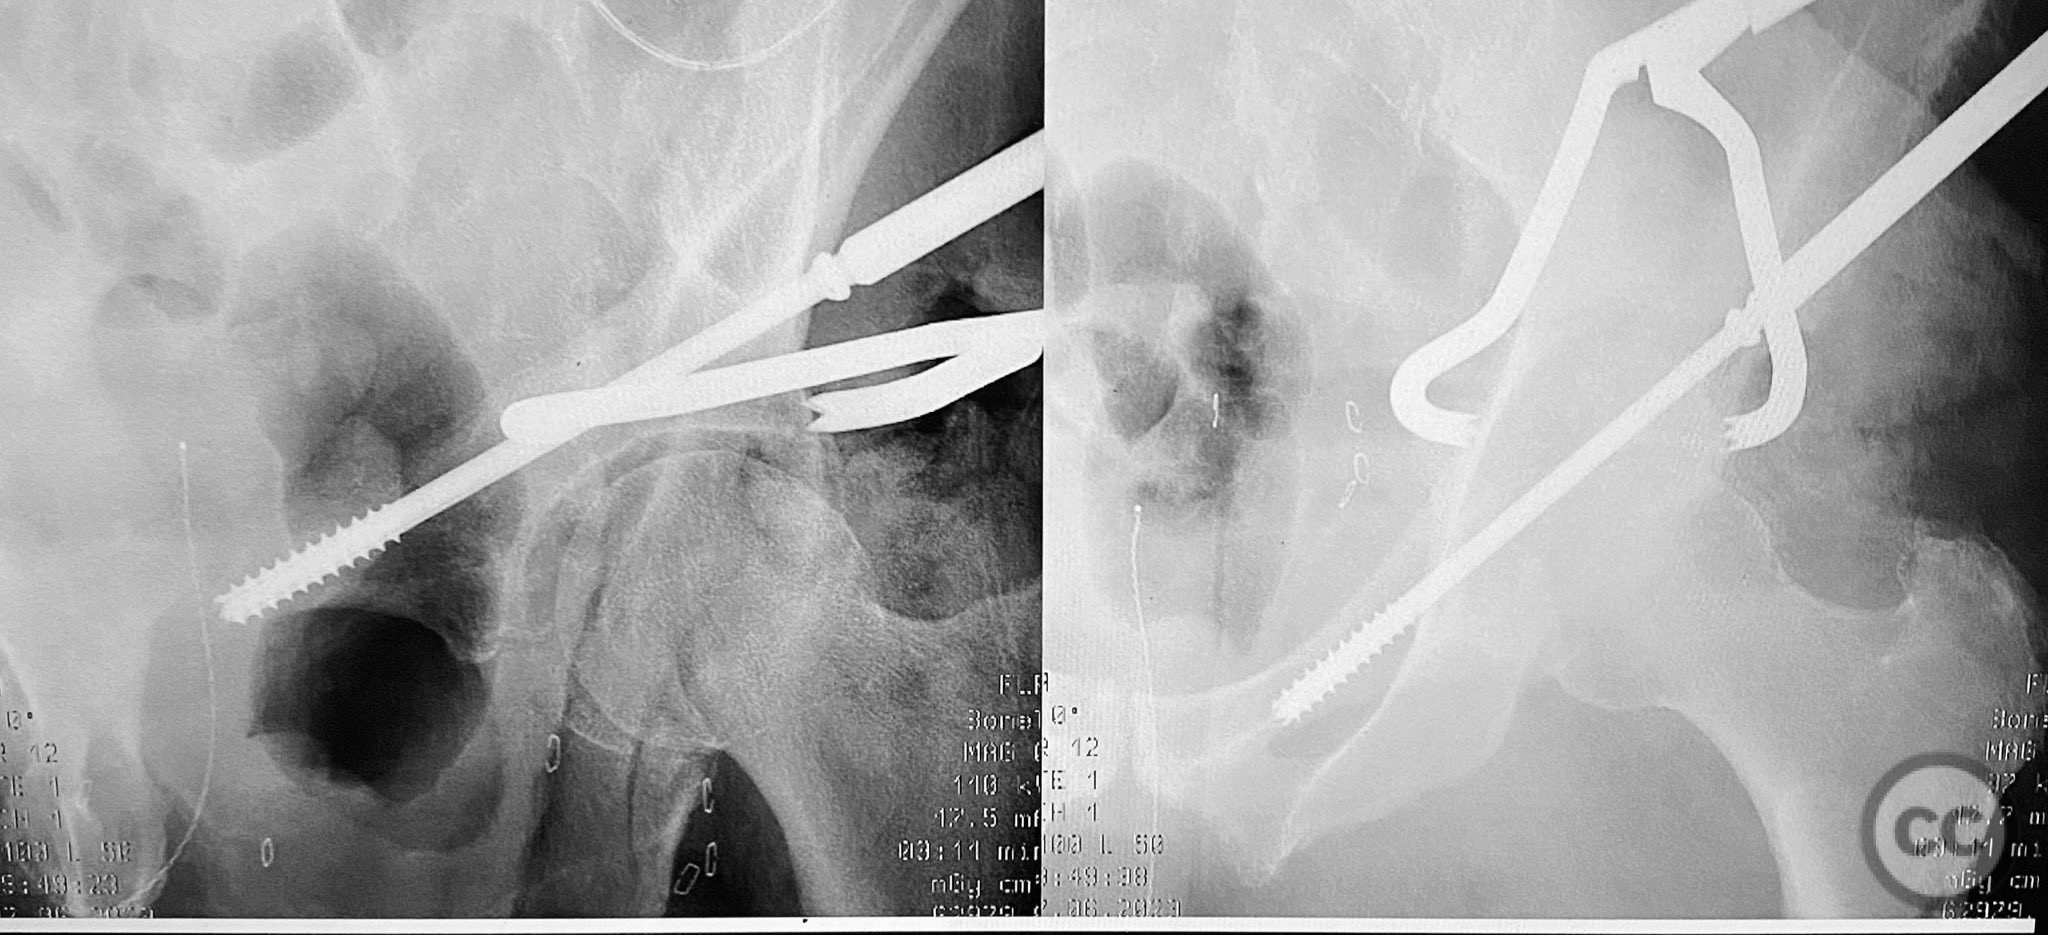

Anatomical surgical approach:  A standard Kocher-Langenbeck approach was performed, incising through the gluteal fascia and splitting the fibers of the gluteus maximus. The short external rotators were identified and protected, with subperiosteal dissection exposing the posterior column and wall of the acetabulum. The sciatic nerve was identified and mobilized laterally. The posterior capsule was found disrupted adjacent to the intact articular surface. The impacted osteochondral fragment was extracted from the joint space. The transverse fracture plane was debrided and reduced using clamps, with a greater trochanteric bone hook employed to manipulate the femoral head beneath the acetabular dome during reduction. Provisional fixation was achieved with a percutaneous lag screw across the transverse component. The peripheral posterior wall fragment was anatomically reduced and stabilized with a contoured plate. The medial wall defect provided access for reduction of the impacted articular segment, which was bone grafted prior to reduction and plating of the medial wall. Capsular tissues were repaired with nonabsorbable sutures prior to layered wound closure.

Operative remarks:

The posterior wall fragments exhibited an unusual caudal hinge morphology, necessitating careful mobilization to avoid propagation or comminution. Removal of the impacted intra-articular fragment was essential to achieve concentric reduction of the femoral head within the acetabular dome. Use of a greater trochanteric bone hook facilitated precise control of femoral head position during reduction maneuvers. The medial wall fragment, though non-articular, allowed direct visualization and accurate reduction of the impacted osteochondral segment, which was supported with bone graft prior to definitive fixation. Repair of disrupted capsular tissues was performed to restore soft tissue integrity and potentially reduce postoperative instability.

Postoperative protocol:   Postoperatively, toe-touch weight bearing was instituted for 8 weeks with active-assisted range of motion exercises initiated immediately. Hip flexion was limited to 90 degrees for 6 weeks to protect capsular repair. Abduction and external rotation were restricted during early rehabilitation. Progressive weight bearing commenced at 8 weeks based on radiographic evidence of healing.

Orthopaedic implants used:   3.5mm pelvic reconstruction plate (posterior wall), 3.5mm pelvic reconstruction plate (medial wall), percutaneous cannulated lag screw, cancellous bone graft